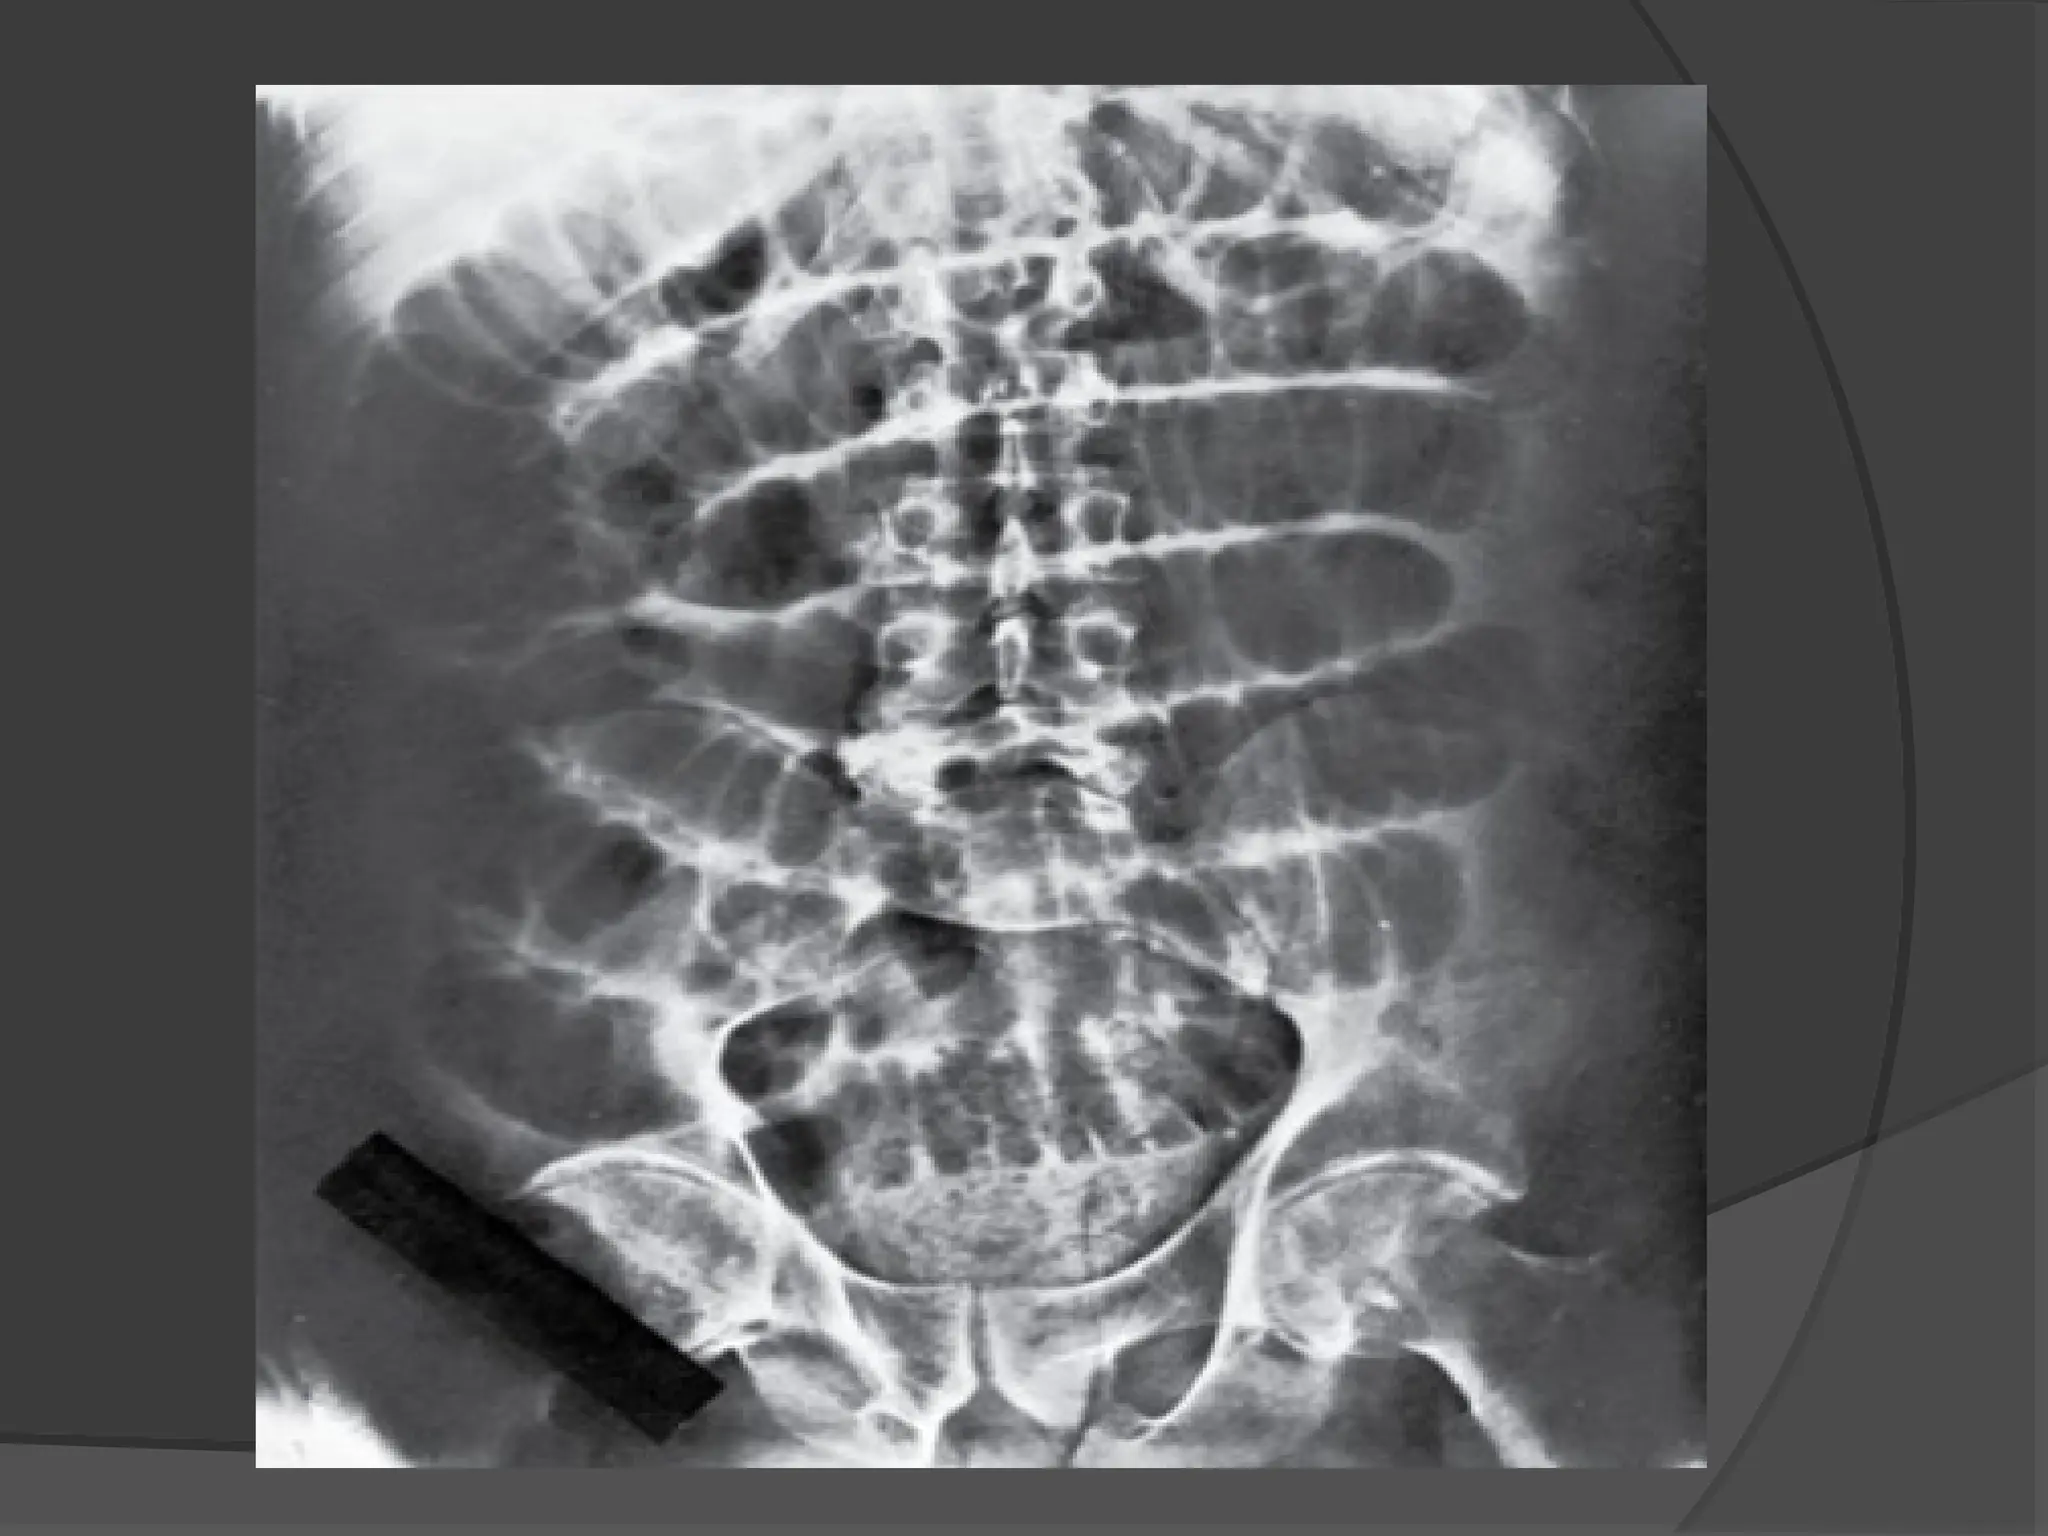

X-RAY

 Small Bowel

Obstruction is

suggested by a

“ladder” pattern, when

obstruction occurs,

both fluid and gas

collect in the intestine.

 They produce a

characteristic pattern

called air-fluid levels.

The air rises above

the fluid and there is a

flat surface at the air-

fluid interface.

 Distended Large

Bowel Tends to lie

peripherally and to

show the

Hustrations of the

Taenia Coli.